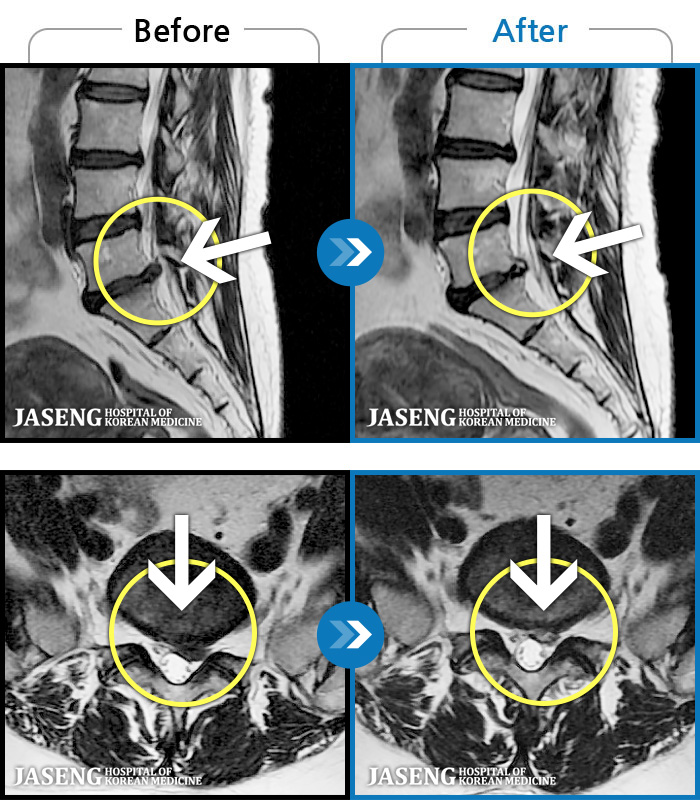

푸쉬업을 여러 번 반복한 뒤 극심한 하요부 통증 및 우측 하지부 저림

2024.03.21 ~ 2024.09.23